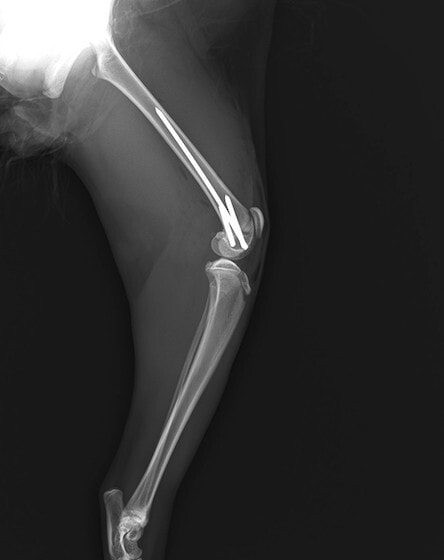

症例3:キルシュナーワイヤーのピンニングによる整復

ペルシャ猫 11ヶ月齢 雄

他院にて左大腿骨遠位の成長板骨折(salter-harrisⅠ型)が認められており、治療相談を目的として来院。当院にて、キルシュナーワイヤーを用いたピンニングにより骨折部位の整復を行いました。術後の経過は良好で、現在も経過観察中です。

術前レントゲン

術後レントゲン

機器

Arthrex社のターゲティングデバイスを用いてピンニングの位置を調整することで、確実な固定を行っています。当院ではこの手術器具以外にも、人の手術にも使用される様々な器具を導入し、手術精度を高め、また医療メーカーと新しい器具の開発、試作にも取り組んでおります。